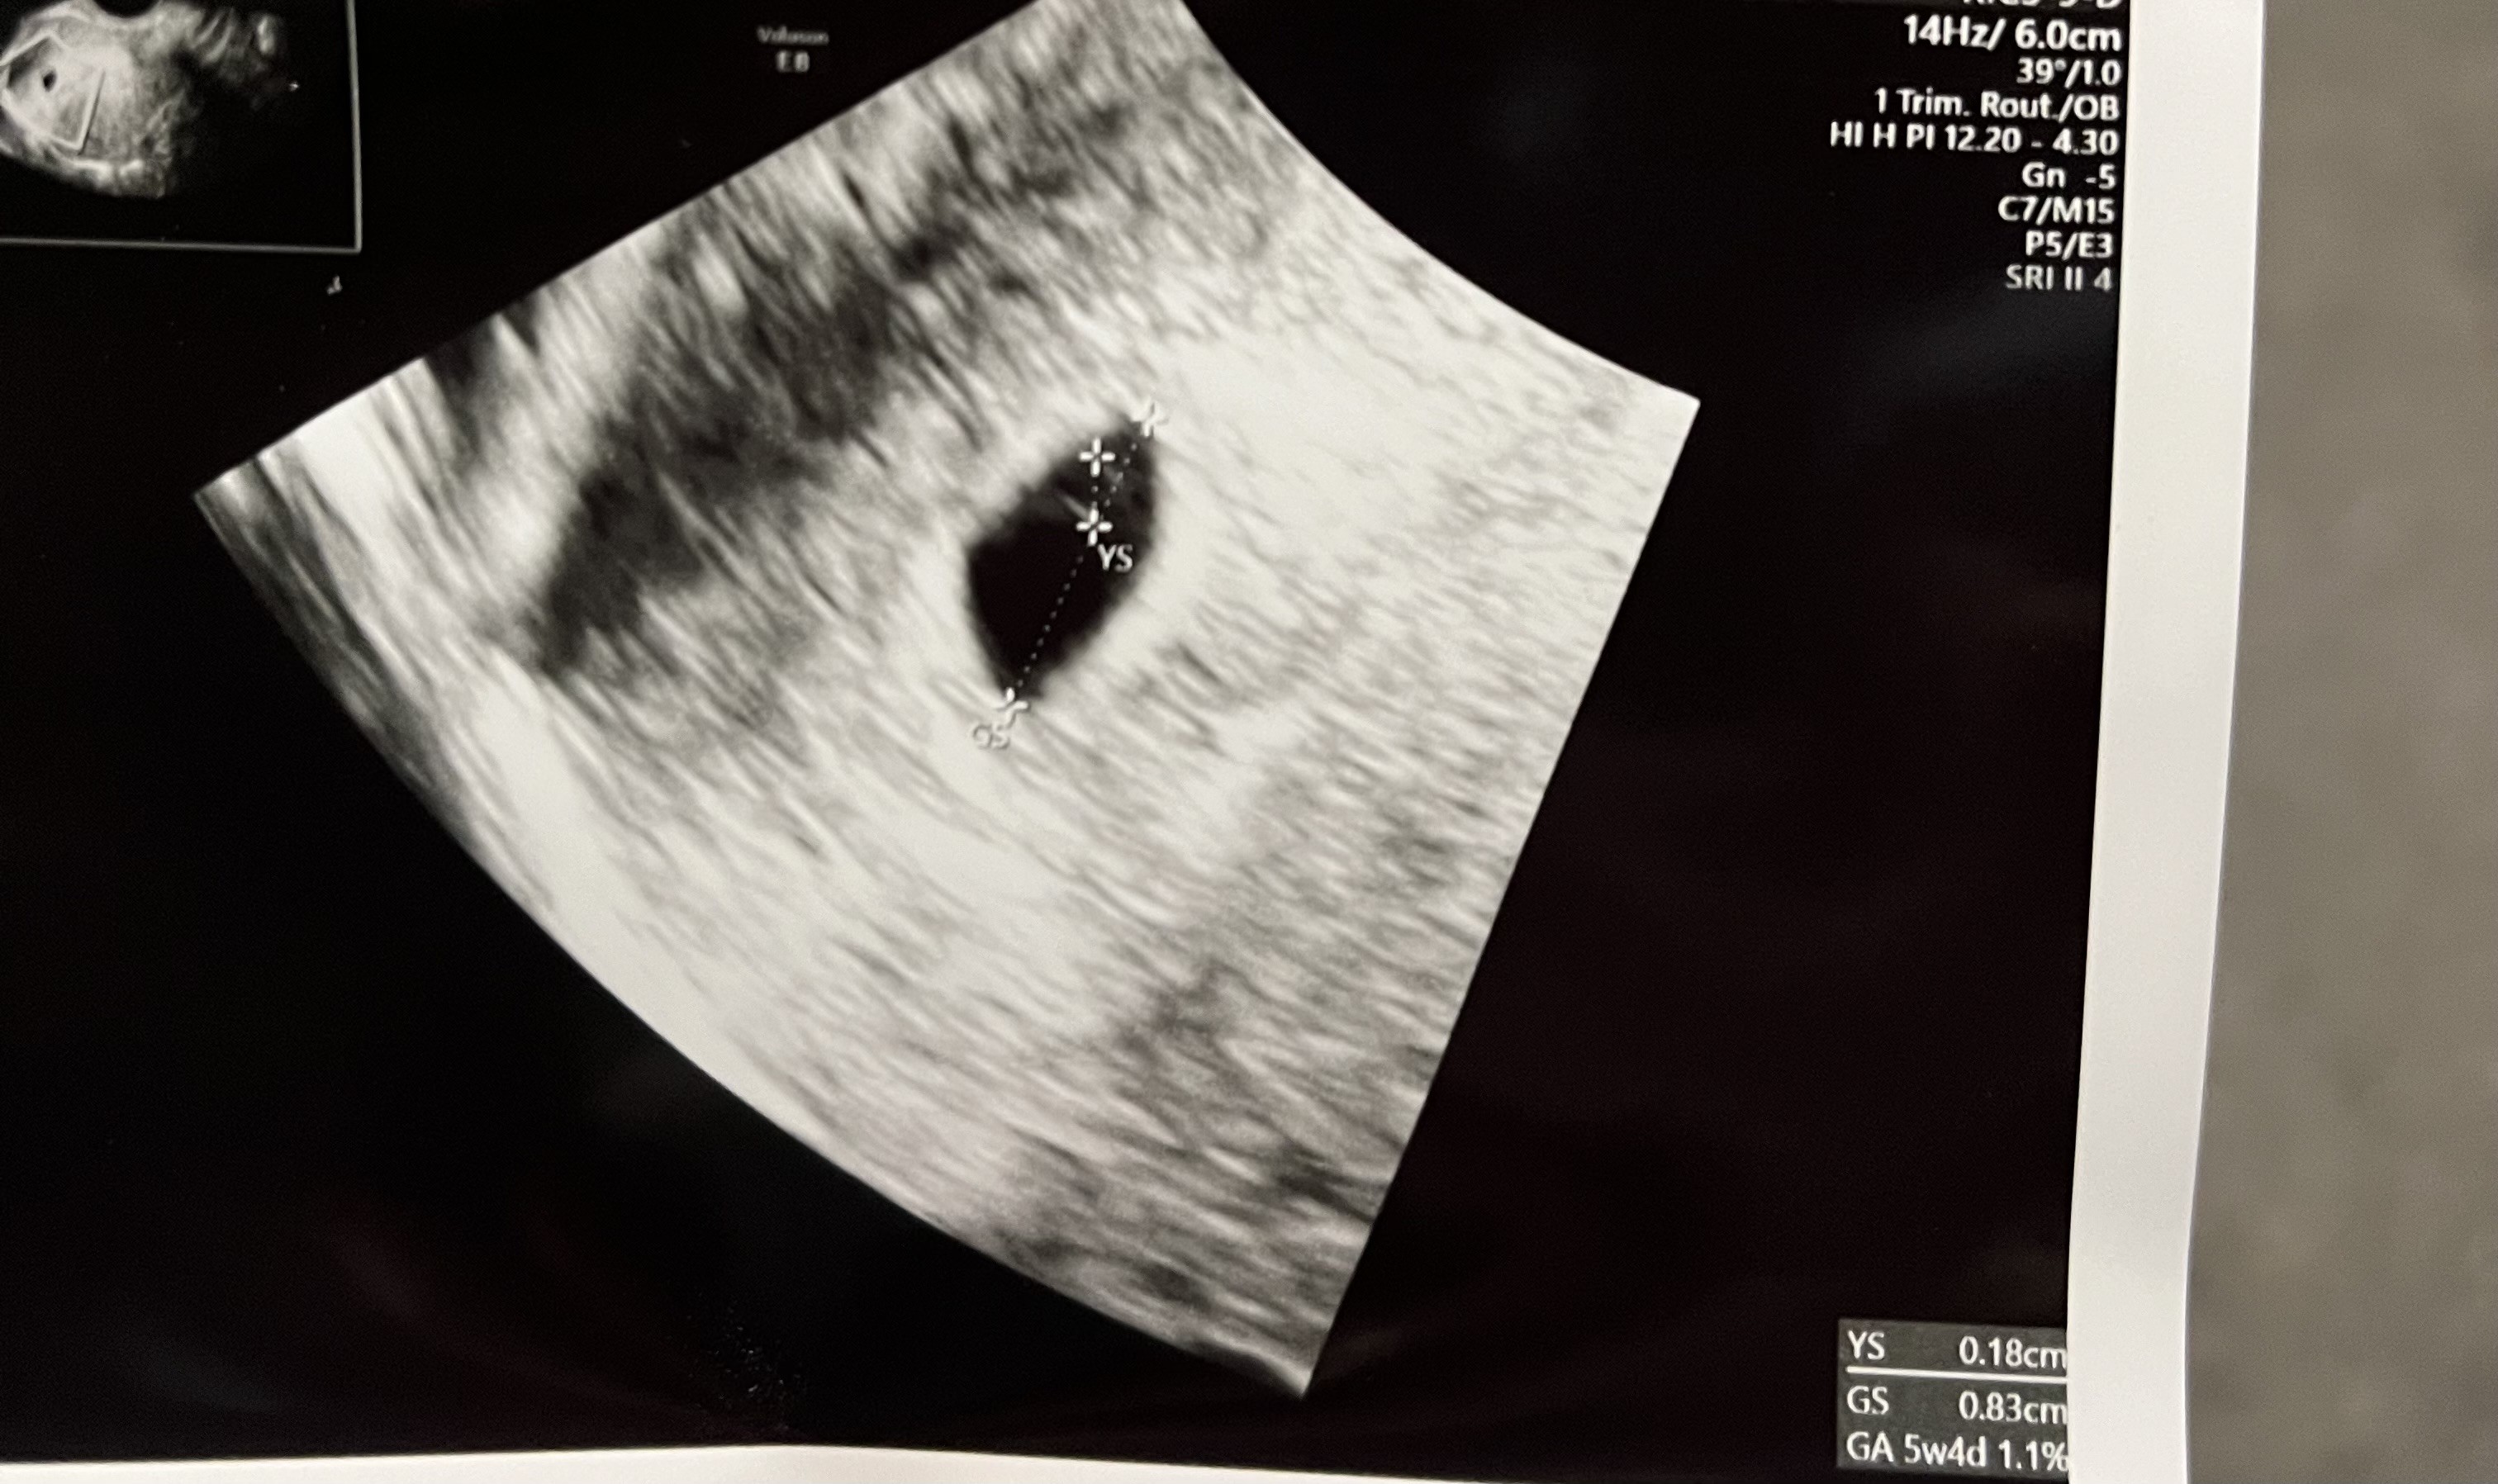

Dziś byłam na pierwszej wizycie w ciąży, owulacja była równe 3tyg temu (dziś jest więc 5+0). I nie ma opcji, by owulacja była wcześniej. Martwi mnie trochę, że w USG już było widać YS, nie powinien się on pojawić trochę później? Poza tym, czy on nie jest za duży w stosunku do GS? YS 18mm, GS 83mm.

806,5 KB · Wyświetleń: 310